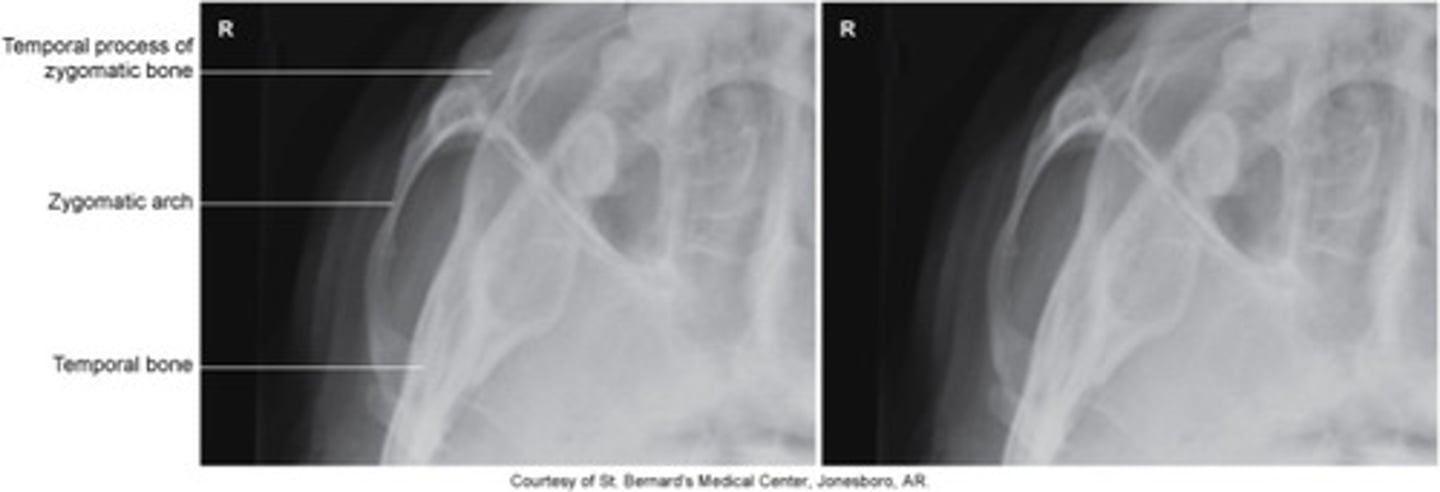

Zygomatic bone

- two zygomatic / malar bones

- temporal process extends posteriorly to join zygomatic process of temporal bone

- maxillary process extends anteriorly to join the maxilla bone

- zygomatic arch

- formed by the union of temporal process of zygoma and zygomatic process of the temporal bone

What is this and how is it formed?

Tangential

- IOML is parallel to the IR / rotate mid-sag plane 15 deg towards the effected side/ center zygomatic arch to IR

- Perp to IOML, center to arch ( 1" posterior to outer canthus )

- 1 zygomatic arch free of superimposition/ find depressed fractures or flat cheek bones

* must do 2 images to show both sides*